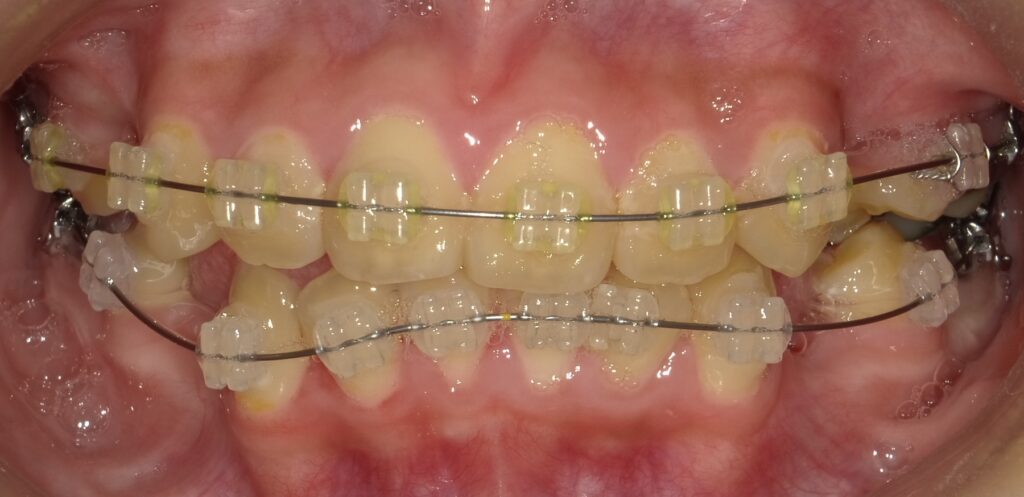

このように全体的なワイヤー装置を装着します。